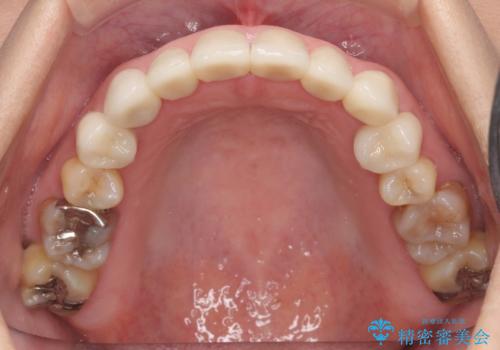

- 前歯の色や形を全体的に綺麗したいといらっしゃった方の症例です。

上顎は左側 4 番目から右側 4 番目までの 8 歯をオールセラミッククラウンで補綴しました。

下顎は左側 4 番目から右側 4 番目までの 8 歯と左下 567 ブリッジをオールセラミッククラウンで補綴し、右下67の銀歯はセラミックインレーによる修復を行いました。